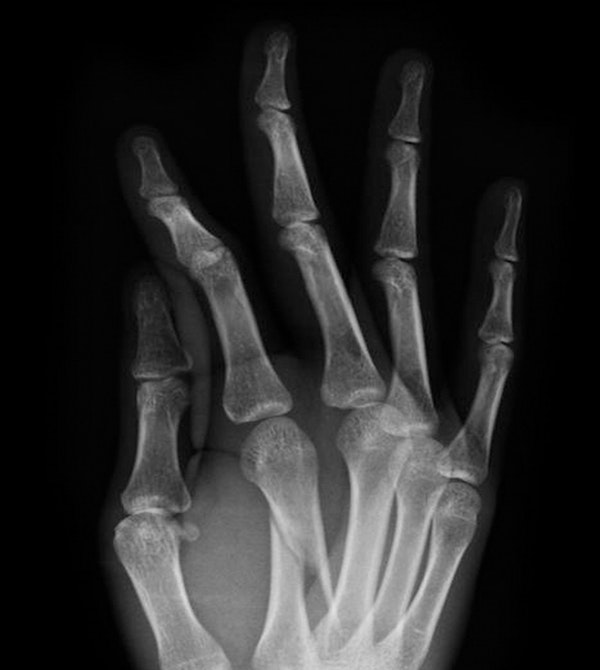

Dr. Vagner specializes in treating issues in the elbow, wrist, and hand. The hand is a remarkably complex system of nerves, tendons, ligaments, and bones, and our surgeon has spent his career studying its intricacies.How does the hand work?

The Anatomy of the Hand

The bones in the hand can break easily due to any number of factors, such as a bad fall, a car accident, or contact sports. If you injured your hand and are experiencing pain and swelling, one of your bones may be fractured and you should seek the attention of an orthopedic physician. If you wait too long to have your hand professionally examined, the bones may heal incorrectly, which can cause long-lasting pain and impaired functionality.

Dr. Vagner is able to diagnose and treat both mild and severe hand fractures at his practices in the Austin, TX, area. He is usually able to set the bone and provide a cast or splint without the need for surgery. In the case of advanced fractures that require surgery, Dr. Vagner uses safe and modern tools and techniques to conservatively repair the hand.